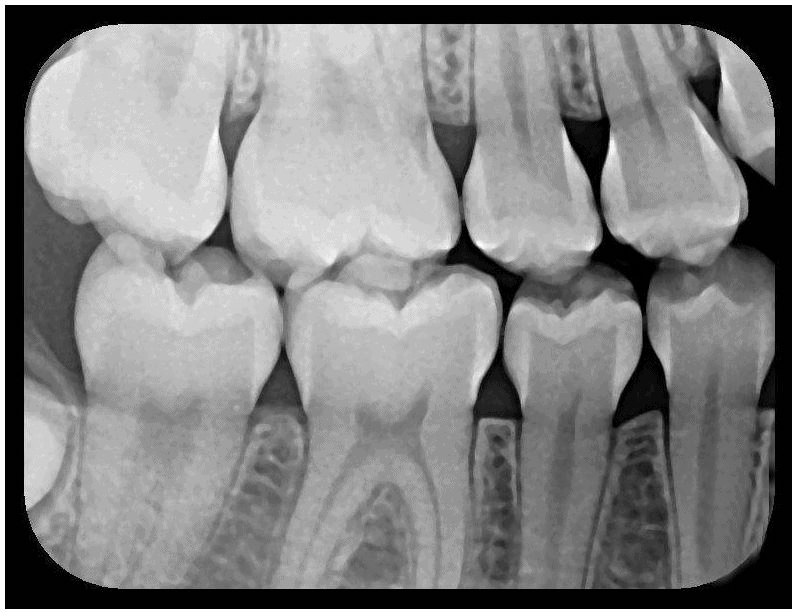

X-Ray 1: How many caries are present?

(Required)

X-Ray 1: How many PAP's are present?

X-Ray 2: How many caries are present?

X-Ray 2: How many PAP's are present?